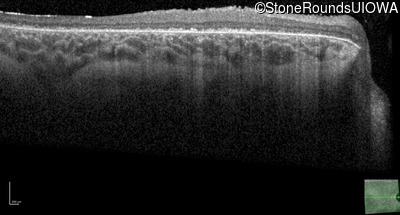

Optical Coherence Tomography - Right - 20/125 +1 sc

Exemplar / OCT Stack

OCT Stack